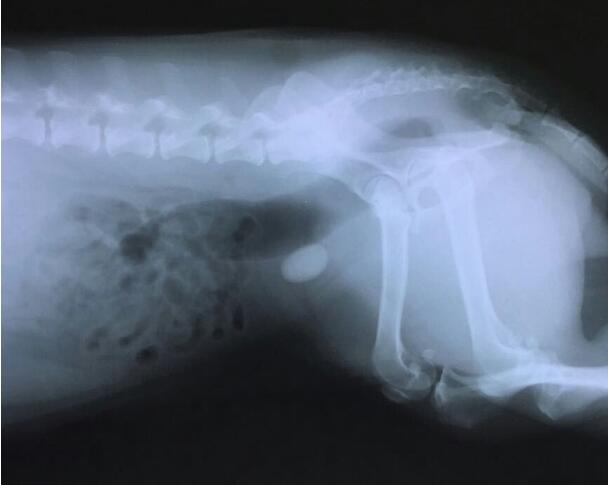

据统计,约有10%左右的狗体内都有狗宝,即使这样但是却很少会听到有关狗宝的消息。因为狗宝是生长在狗的胃里,那如果不通过医学器械检查的话,怕是难以发现狗狗的体内是否有狗宝的。但是通过仔细观察我们还是可以发现狗体内是否有狗宝的一些端倪的。